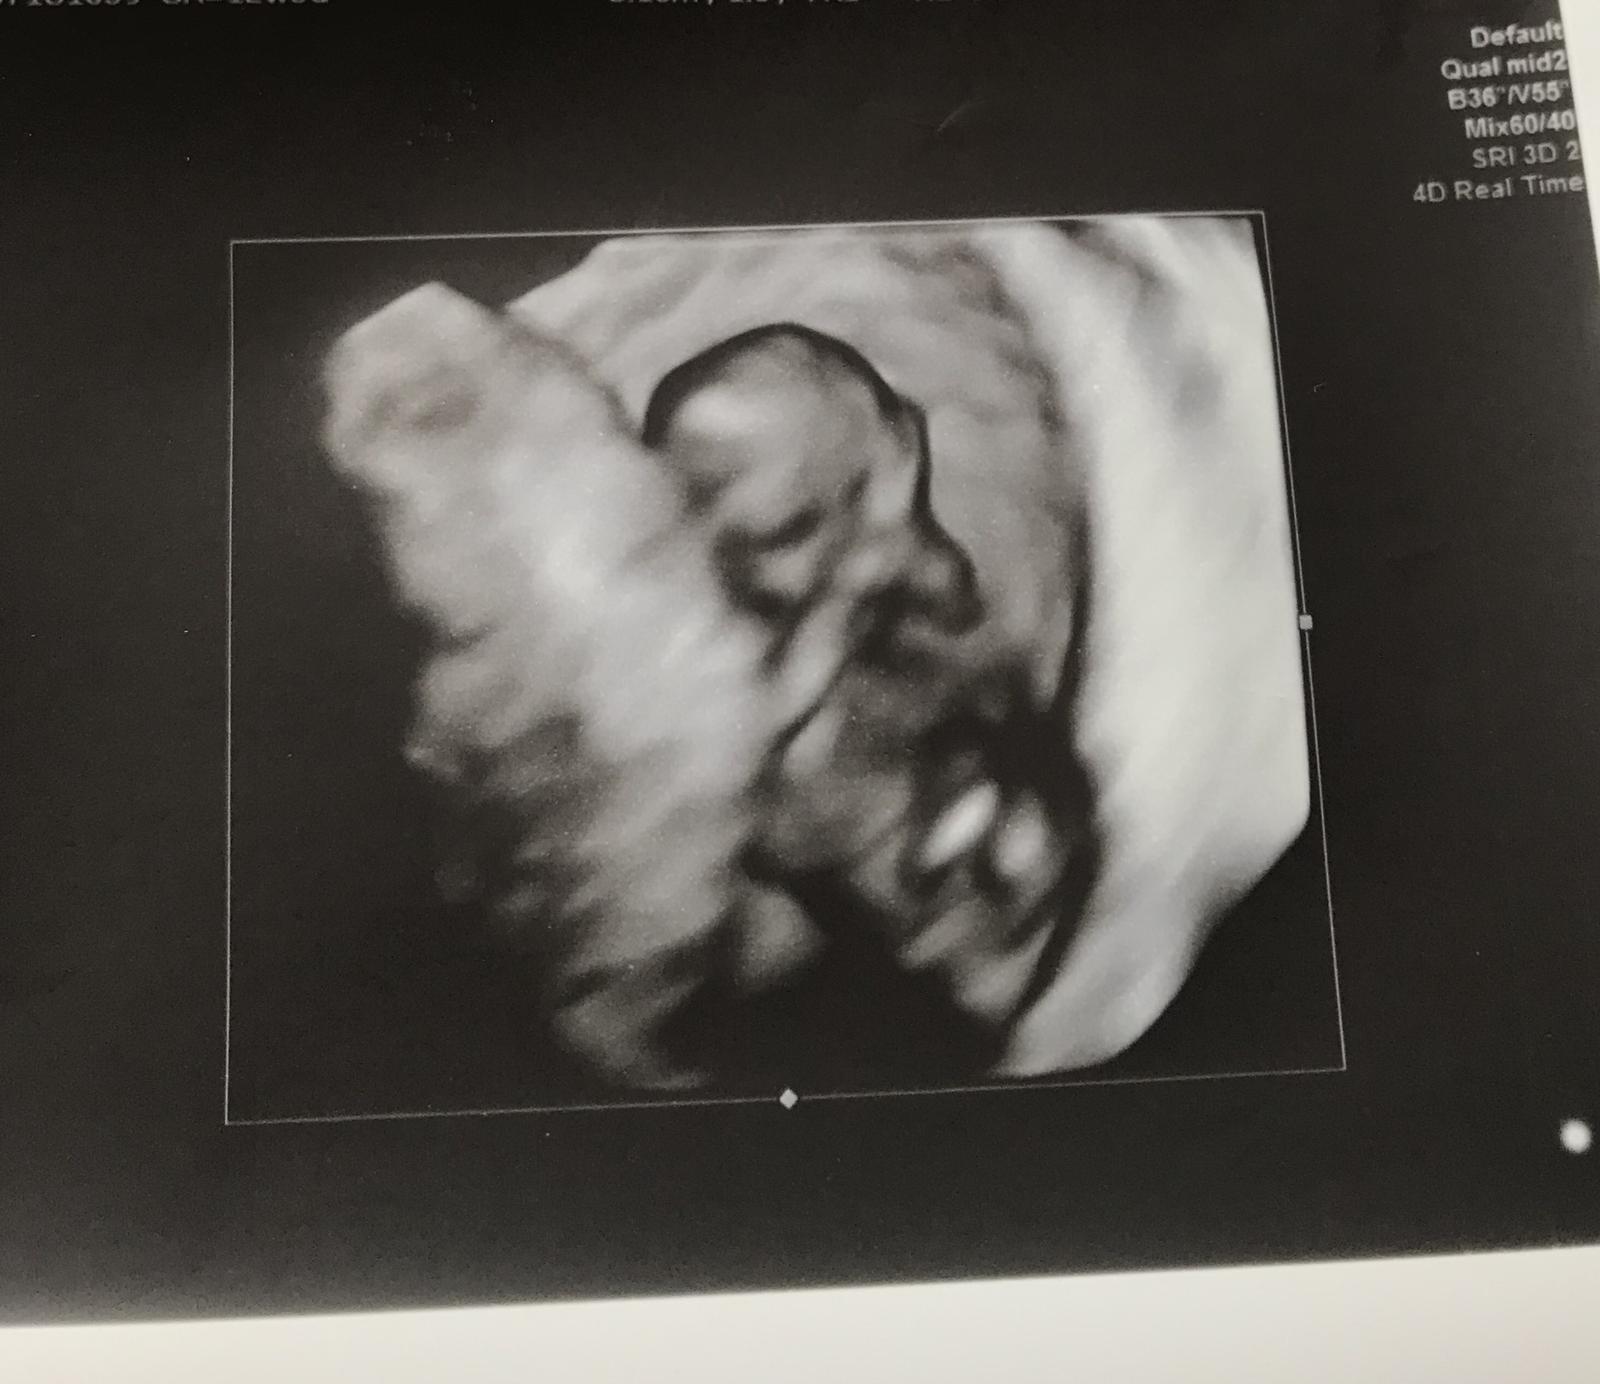

@zvedava_cica tak to vyzera ze je tam ✊

@mini007 jeeeeeej to je kraaaasne

@zvedava_cica toto je určite tehu 😉Veľmi držím palce!